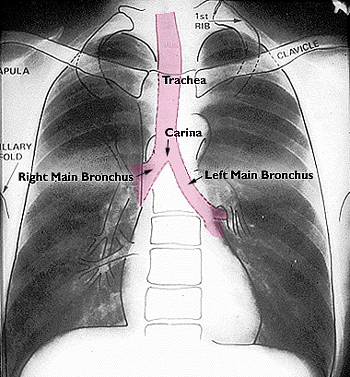

The carina is where the pink tube splits in two, in case you’re like me and need everything explained like you’re five. It seems like you should be able to clearly pick this branch point out, right? Especially if you know roughly where it’s supposed to be. In lecture, Mr. Excited Radiologist demonstrated the branches with some helpful lines, which I have replicated here (same normal X-ray as before):

Do you see? No? Well, you should! Obviously the carina is right there for the taking, you idiots.

(I have looked at this x-ray until my eyes hurt. I see absolutely nothing. Maybe the carina is a mythical creation, like the PMI on the cardiac exam.